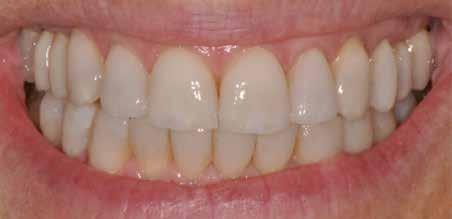

A fogazat elhasználódása alatt azoknak a degeneratív folyamatoknak az összesített hatását értjük, melyeken az élet során a szervezet keresztülmegy. Ezek lehetnek a fogérintkezések közben fellépő mechanikai erők (abrázió, attríció), endogén vagy exogén eredetű savas közegek által kiváltott kémiai behatások (erózió), kariogén baktériumok által okozott pathológiás folyamatok és parodontális elváltozások, valamint iatrogén ártalmak.

A felnőtt páciensek kezelése során általában egyszerre több ellátásra szoruló elváltozást is diagnosztizálhatunk: hiányzó fogak, kopott fogazat, esetleg régi, nem megfelelő, sérült fogpótlások, rendellenes helyzetben lévő fogak stb… Ezen páciensek kezelésekkel kapcsolatos kérései mindig az esztétikai vagy a rágással kapcsolatos kívánságaik kielégítését szolgálja. A kezelések során a fogorvosoknak nem csak a páciensek kéréseinek teljesítésére, hanem ezzel egyidejűleg a fogazat általános megjelenésének és funkciójának lehetőség szerinti javítására is törekedniük kell. Mindemellett a lehető legtöbb saját foganyag megőrzését és az évek során elvesztett kemény- és lágyrészek pótlását (pl.: hiányzó fogak, sorvadt állcsontgerinc, lágyszöveti defektusok) is szem előtt kell tartaniuk, úgy, hogy közben egy hosszú távon fenntartható eredményekkel járó kezelési tervet állítanak össze. Ezek mindig összetett esetek. Annak érdekében, hogy a fentiekben megfogalmazott összes kezelési célt teljesíteni tudjuk, interdiszciplináris megközelítésre van szükség. Az ilyen komplex rehabilitációs kezeléseket „fogászati megfiatalításnak” nevezzük. Ezeknek a beavatkozásoknak lényege az elhasználódott fogazat biológiai szempontokat figyelembe vevő minimál invazív módon történő helyreállításában rejlik, mely folyamat végére a páciensek fogai visszanyerhetik fiatalkori megjelenésüket.

A rehabilitációs kezeléseknek a célja, hogy a páciensek a lehető leghosszabb időn keresztül képesek legyenek mosolyogni és rágni. A protetikai kezeléseket végző fogorvosoknak helyre kell tudni állítaniuk a fogívek szabályos lefutását és az alsó és felső fogív között megfelelő interokkluzális érintkezéseket kell létrehozniuk. Így lehet csak az ellátás befejezését követően elért végeredmény biológiai szempontokat figyelembe vevő esztétikáját, funkcionális megfelelőségét, hosszú távú fenntarthatóságát biztosítani.

A fogszabályzó kezelések egyik legfontosabb célja, hogy elérjük a lehető legharmonikusabb interokkluzális fogérintkezéseket, továbbá az állcsont relációs helyzetének frontális és szaggitális síkban is megfelelőnek kell lennie. A fogszabályzás befejezésekor a fogpozícióknak nem orthodonciai, hanem protetikai szempontok szerint kell ideálisnak lenniük. Az Invisalign ClinCheck szoftver (Align Technology) segítségével a protetikus az orthodontussal együtt meg tudja határozni azokat a végső fogpozíciókat, amelyek a lehető legjobb végeredmény biztosításához elengedhetetlenek. Bizonyos klinikai paramétereket, mint a fogak klinikai koronájának nagyságát, az egyes fogak fogíven belüli optimális pozícióját, a fogívek egymáshoz viszonyított helyzetét, a fogak között látható rések nagyságát, a frontfogak tengelyének dőlését, az overjet és overbite mértékét már a kezelések megkezdése előtt pontosan definiálni kell. Ezeket az adatokat viszont csak a tervezett végleges fogpótlás ismeretében lehet meghatározni, ezért van szükség az orthodontus és a protetikus szoros együttműködésére.